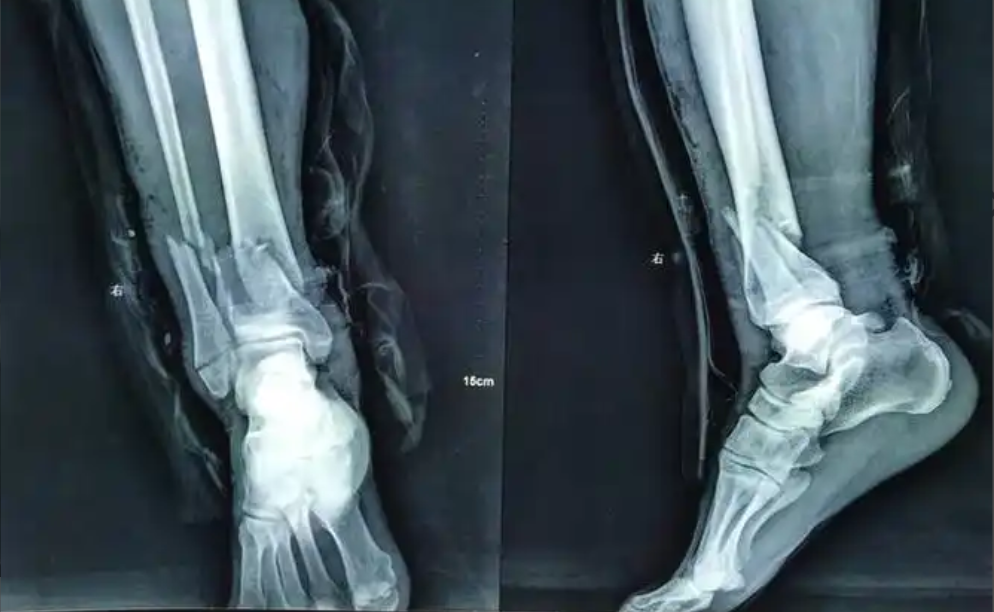

在临床中,医生会通过X线检查观察骨折线周围是否出现“模糊影”,这是纤维软骨痂形成的影像学特征。此阶段患者可在医生指导下进行轻微的肌肉收缩训练,如握拳、股四头肌收缩等,以预防肌肉萎缩,但需避免骨折部位受力。

根据骨痂形成的来源,可分为内骨痂和外骨痂:内骨痂形成于骨折断端的髓腔内,外骨痂则形成于骨折断端的外周,两者共同包裹骨折部位,使骨痂强度大幅提升。当原始骨痂形成后,骨折线在X线片上会变得模糊甚至消失,患者可逐渐开始负重训练,但需遵循“循序渐进”原则,避免突然受力导致骨痂断裂。